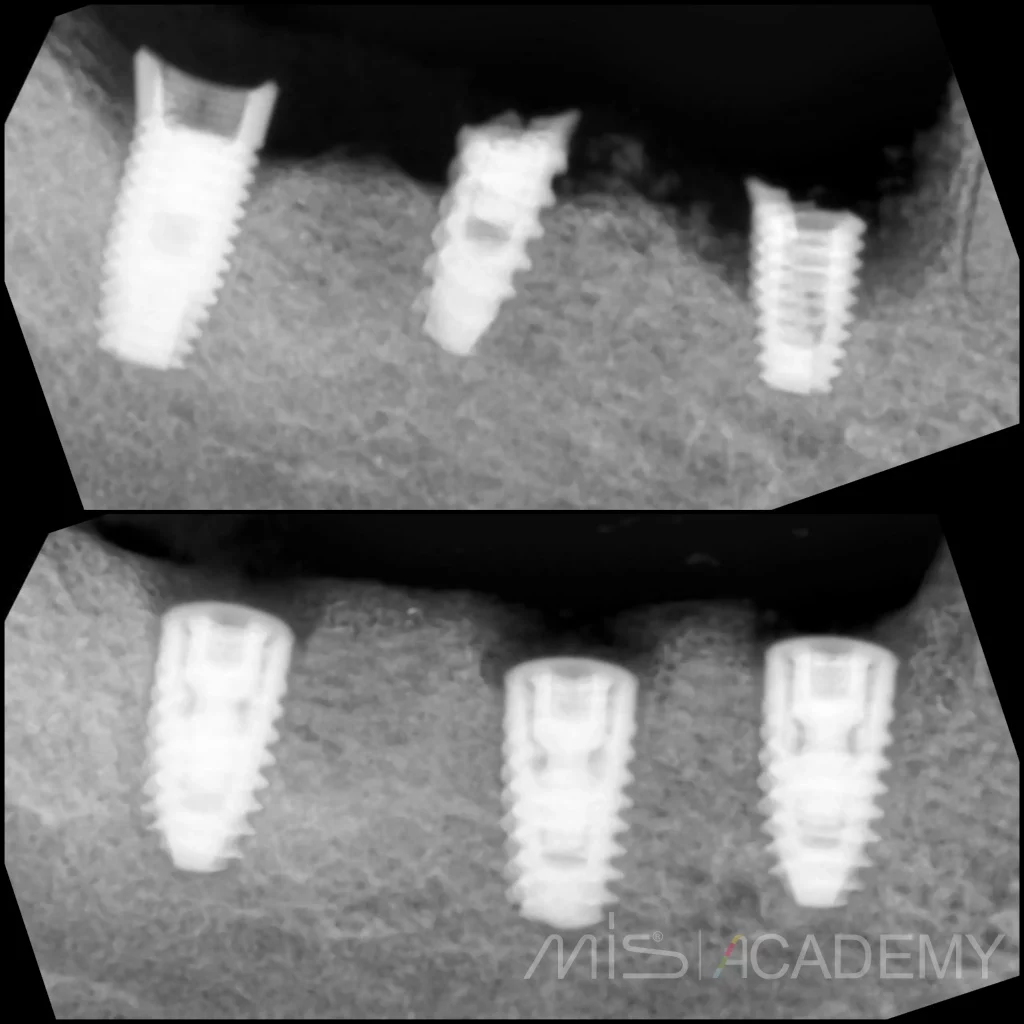

— Установка имплантов MIS C1.